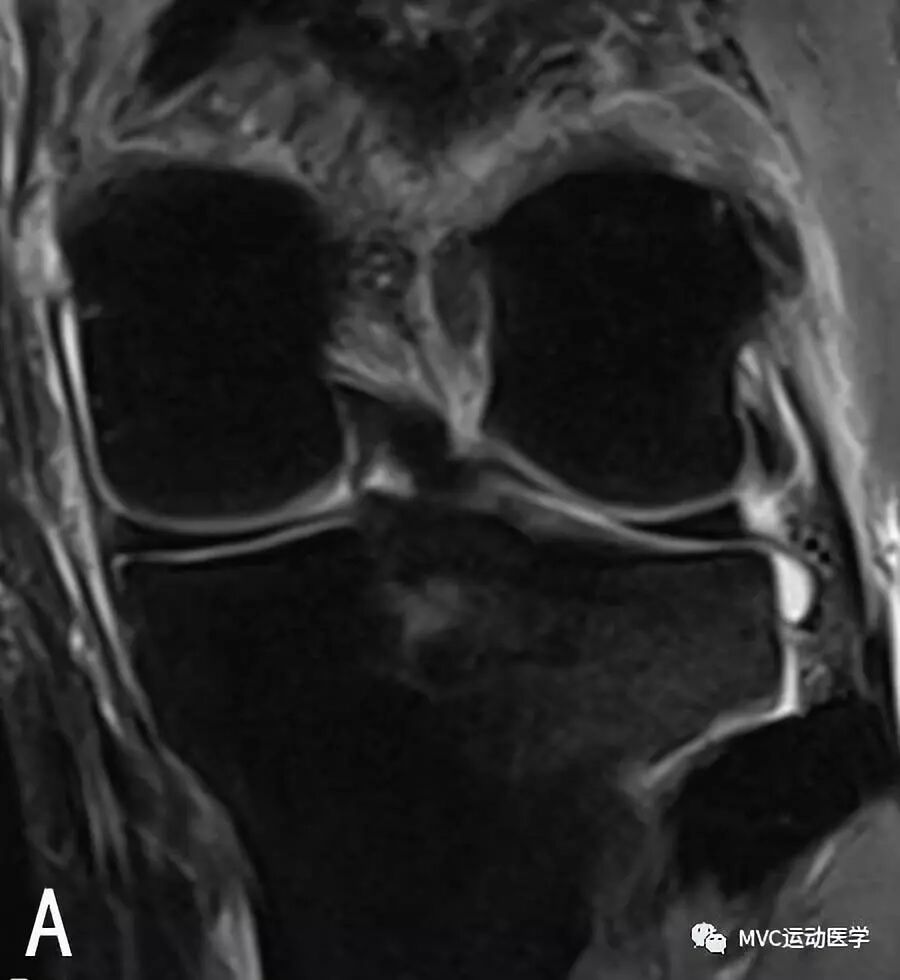

A:冠状位MRI显示腘肌腱裂孔(白色宽箭头)与腘肌腱(白色细箭头);

B:冠状位MRI显示腘肌腱(白色箭头)穿过腘肌腱裂孔;

C:矢状位MRI显示腘肌腱(白色箭头),

D:矢状位MRI显示腘肌腱(白色箭头)